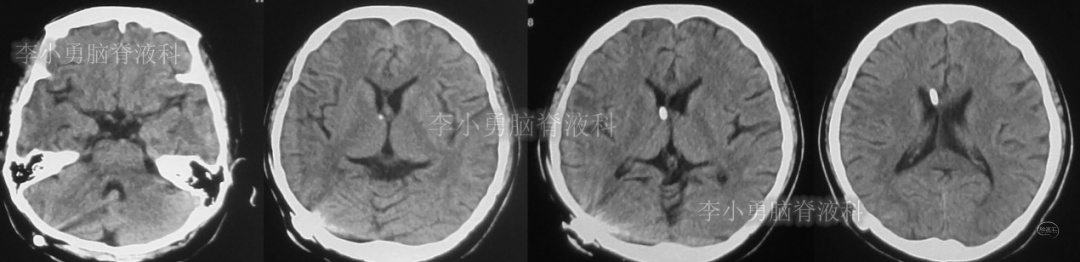

患者于2018年1月29日,突发头痛、头晕、恶心、呕吐,并高热40度。在当地医院门诊输入4天抗生素后发热缓解,但出现了双眼不能上视(眼球不能向上看)。5天后即2018年2月3日,在当地的第1家医院:浙江省海宁市某医院行头颅CT(图-1)发现脑室扩张,当地医院诊断为“梗阻性脑积水”。

图-1:2018年2月3日头颅CT